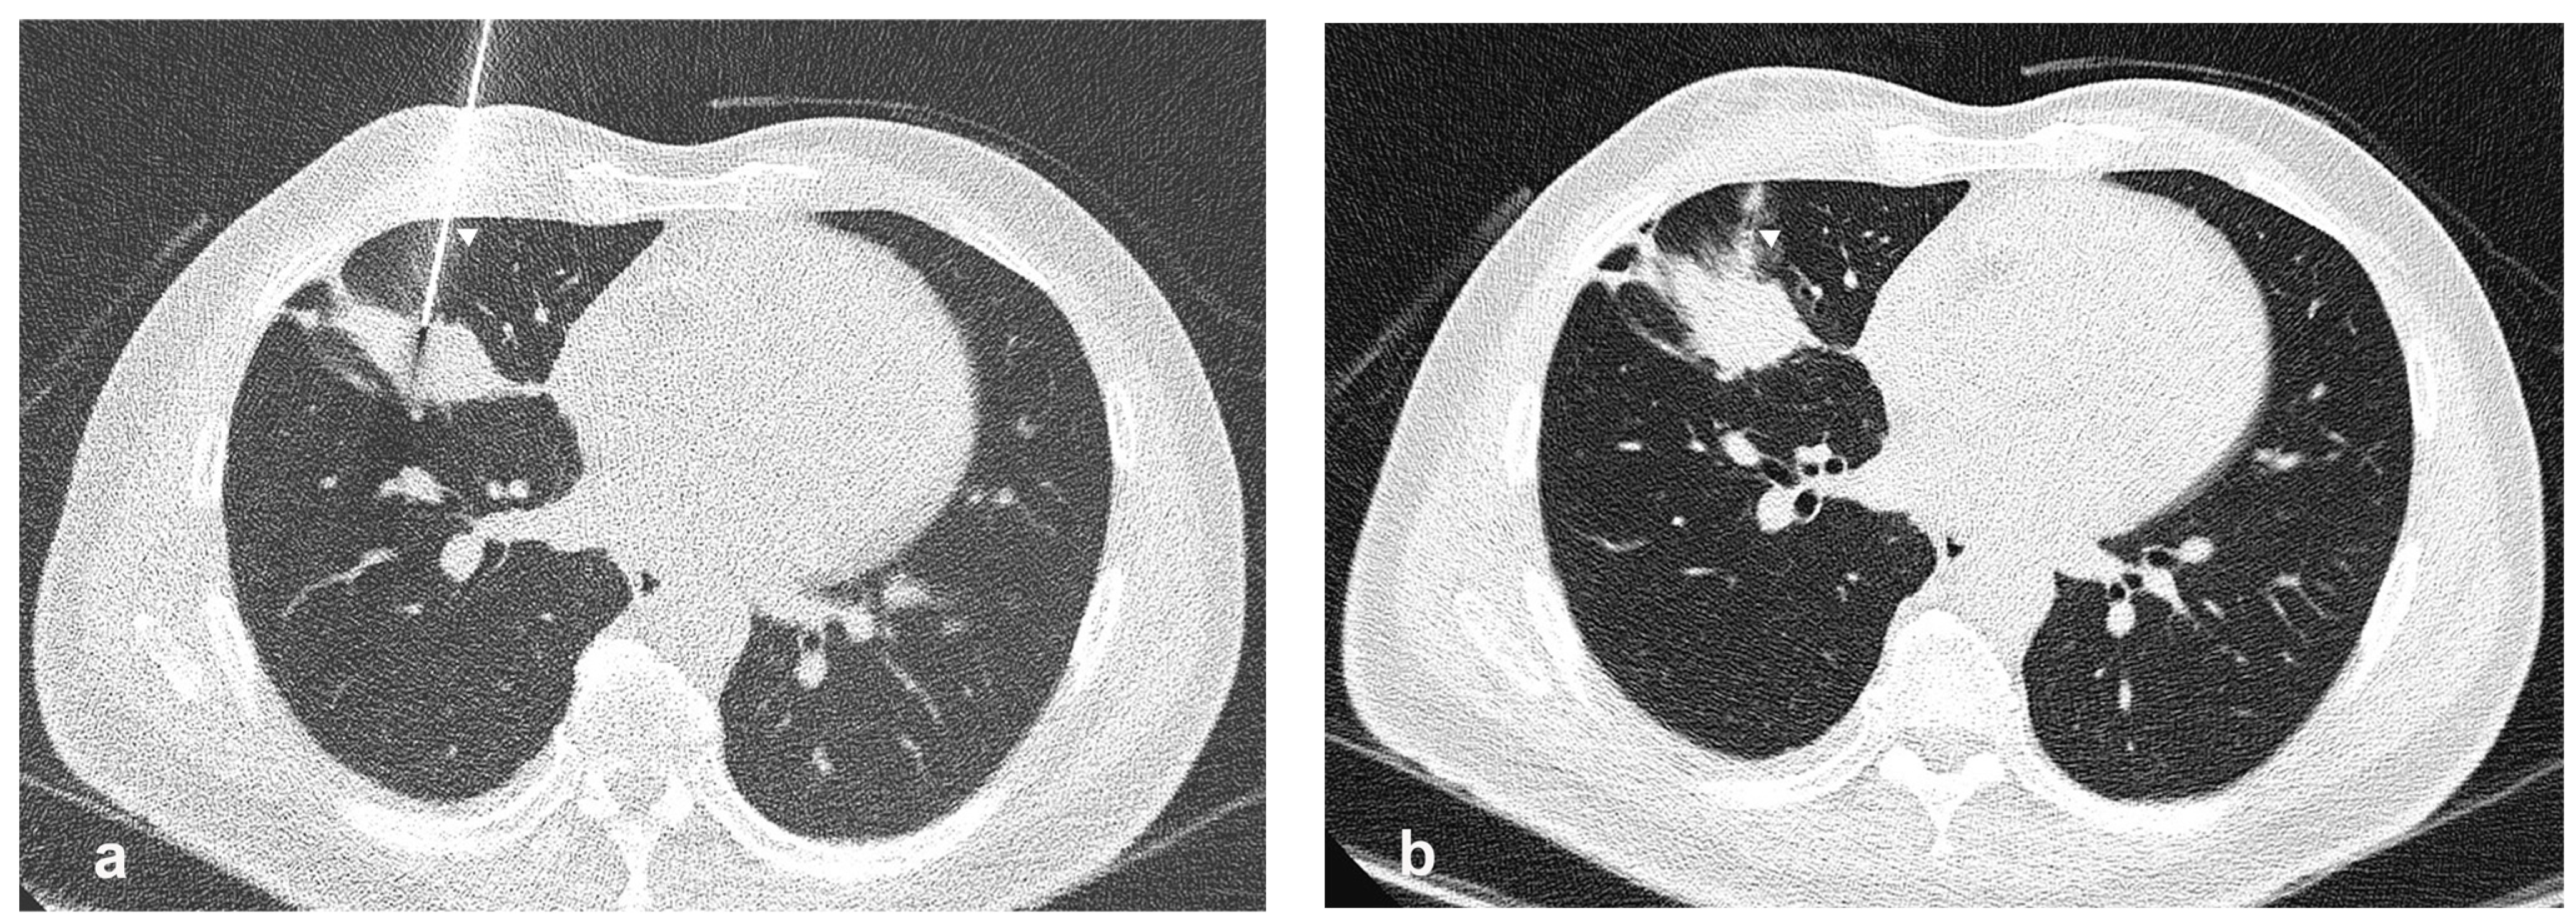

- Procedure technique